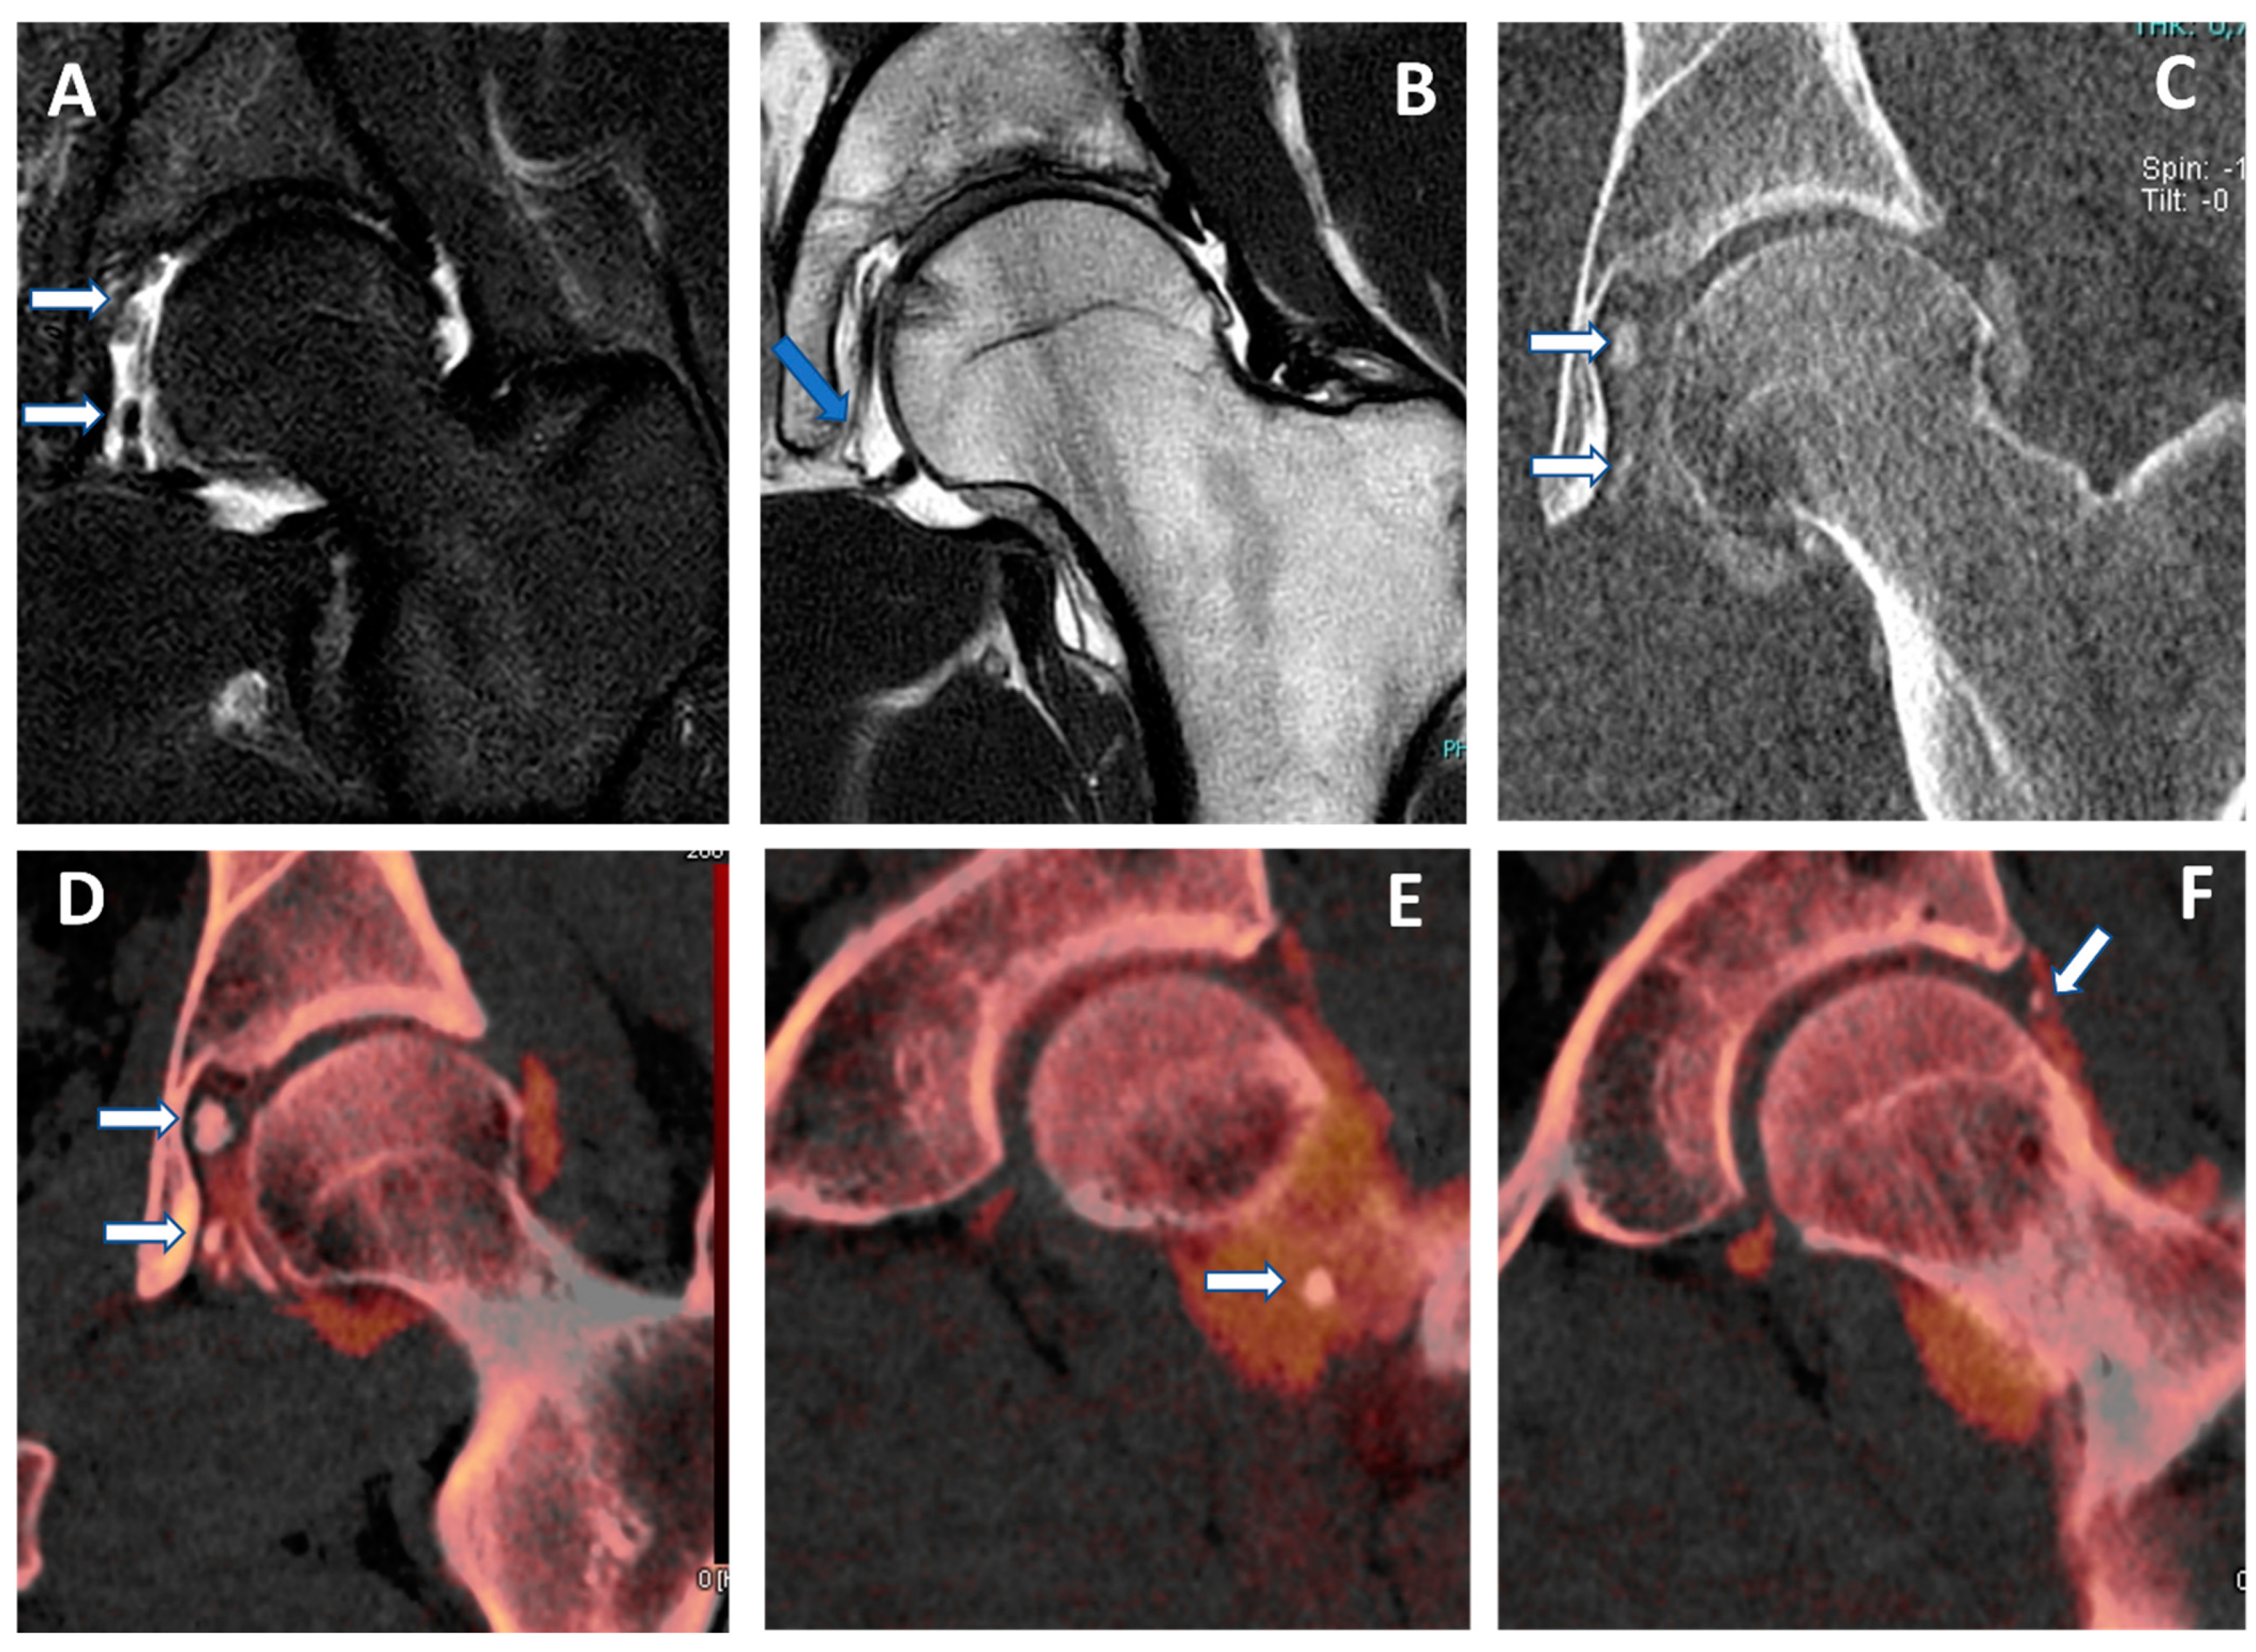

Figure 5.

Capsular, labral, and loose calcifications in femoro-acetabular impingement. On MRA coronal STIR and T1 weighted images (A,B), it is possible to recognize subtle filling defects (arrows on (A)) and capsular thickening (blue arrow in (B)). On the DECTA VMI 1 mm coronal reconstructed image (C), calcifications are partially and erroneously subtracted (arrows). The corresponding DECTA iodine map images (D–F), reconstructed on the coronal plane (1 mm thickness), clearly show the presence of loose bodies and capsular and labral calcifications (arrows).

In our experience, both VMI and VNC images from iodine maps can be used to enhance the identification of loose bodies and to distinguish calcifications from non-calcified loose bodies. Moreover, these applications can be employed, alone or in combination, to avoid potential pitfalls, such as tendon or labral calcifications (that may mimic the passage of contrast material in the case of a subtle tear) or the abnormal accumulation of highly concentrated contrast material in a distal articular recess, simulating the presence of intra-articular calcifications (Figure 5).